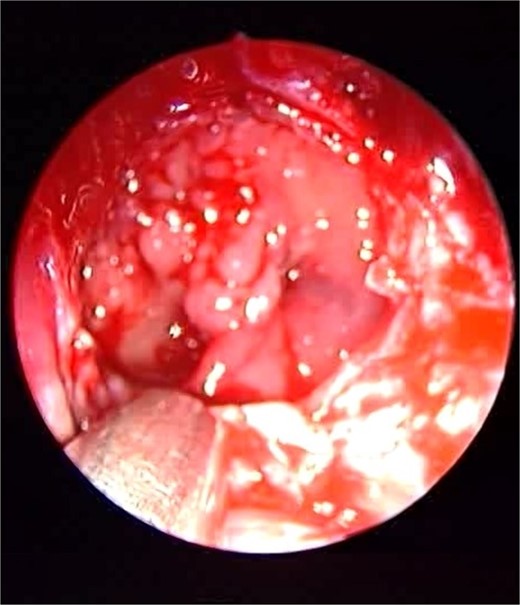

Endoscopic intraoperative view of the sphenoid sinus full of fungal mud and mucin.

Patient presented to the emergency department with four days history of sever left side headache associated with nausea and vomiting, and nasal discharge with on\off nasal obstruction. Two days history of diplopia with lateral gaze of the left eye, with decrease the visual acuity. Ophthalmologic examination revealed left abducens nerve palsy. Other neurologic examinations were within normal. Endoscopic nasal examination revealed left multiple grade two nasal polyps occupying the middle meatus. Pre-operative brain computed tomography (CT) shows bilateral near total opacification and expansion of the paranasal sinuses and nasal cavity (Fig. 1). Additionally, there is evidence of invasion of the left cavernous sinus with encasement of cavernous segment of left internal carotid artery (ICA). Furthermore, pituitary gland and optic chiasm displaced superiorly. Magnetic resonance imaging revealed that the sphenoid sinus is expanded and bulging superiorly into the pituitary fossa causing displacement of pituitary gland and stalk without mass effect upon the optic chiasm (Fig. 2). It extends laterally causing effacement of the cavernous sinus and left Meckel’s cave. No evidence of intracranial extension. The patient underwent functional endoscopic sinus surgery with computer-assisted navigation system. Intraoperatively, sphenoid sinus was full of fungal mud and mucin (Fig. 3). The polyps were removed completely from the nasal cavities, fungal mud, and mucin were removed from the sinuses (Figs 4 and 5). Patient had dramatic improvement after surgery, the rhinosinusitis symptoms are resolved, the diplopia has been improved, and the paranasal sinuses were clear. The patient was discharged with topical corticosteroid and saline irrigations.